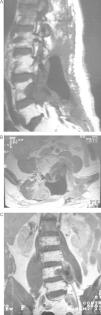

El fibrosarcoma epitelioide esclerosante (SEF) es una variante poco frecuente de fibrosarcoma de bajo grado con características histológicas e inmunohistoquímicas bien definidas, caracterizado por su mal pronóstico. Presentamos un caso de SEF a nivel paraespinal en un paciente varón de 49 años con un tumor que se extiende hacia el foramen L4-L5 e invade la raíz L5. La histología de la pieza quirúrgica y el estudio inmunohistoquímico fueron compatibles con SEF. Este caso es particularmente inusual por su origen a nivel paraespinal e ilustra, a pesar de su bajo grado, el potencial de malignidad del SEF.

Sclerosing epithelioid fibrosarcoma (SEF) is a rare variant of low-grade fibrosarcoma, with specific histological and immunohistochemical features and a poor prognosis. We report a case of SEF of the paravertebral column in a 49-year old male who presented a paraspinal mass with extension into the L4-L5 neural foramen and invasion of the L5 nerve root. Histology of the tumourectomy specimen and its immunohistochemical study led to the diagnosis of SEF. This case was particularly unusual due to its paravertebral column location and, despite its low grade, illustrates the malignant potential of SEF.